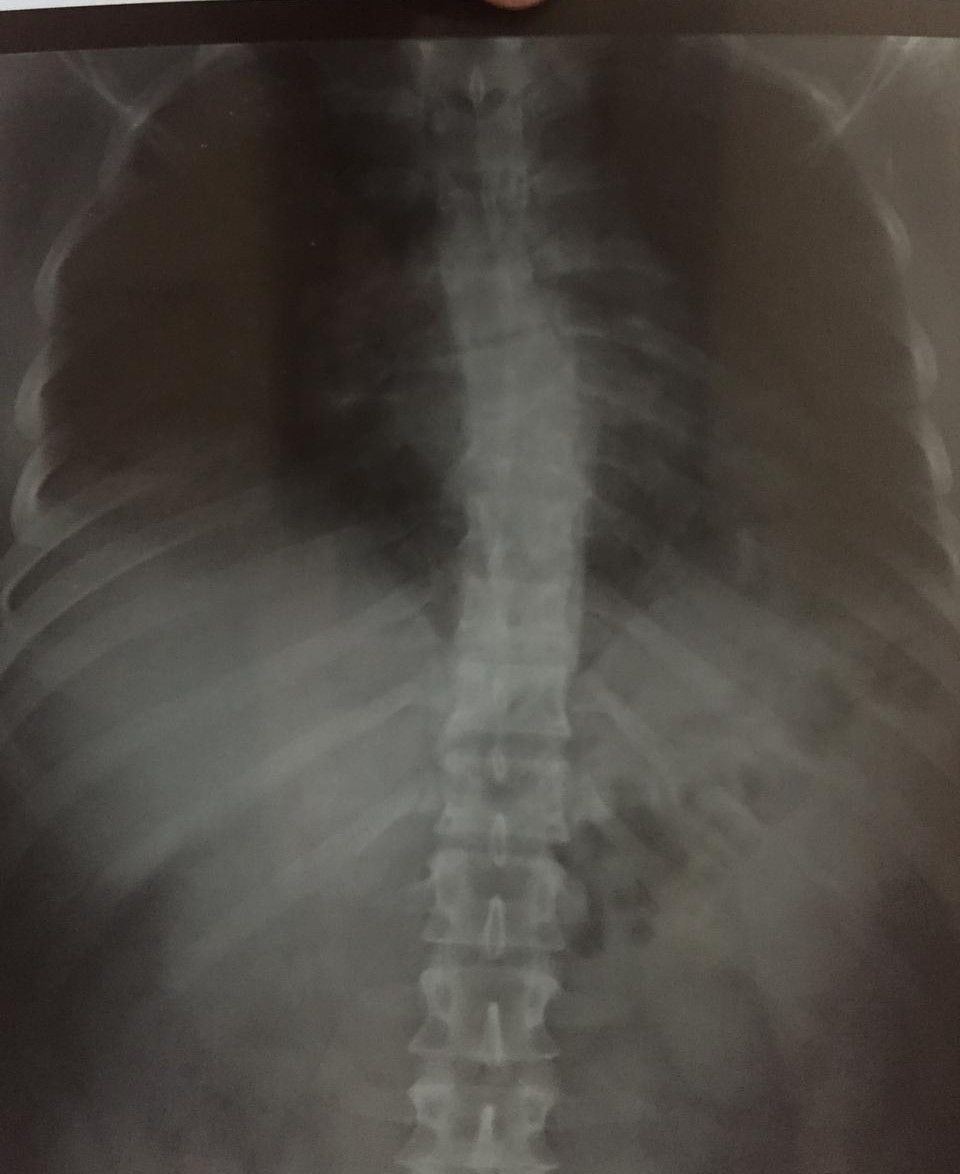

22 yr old male Patient came with complaint of pain in the thoracic spine since 3 months No history trauma or injury Pain is intermittent and increase on work Diagnosis?

T566 Inter vertebral space obliterated Scoliosis+. Trivial TB vertebrae